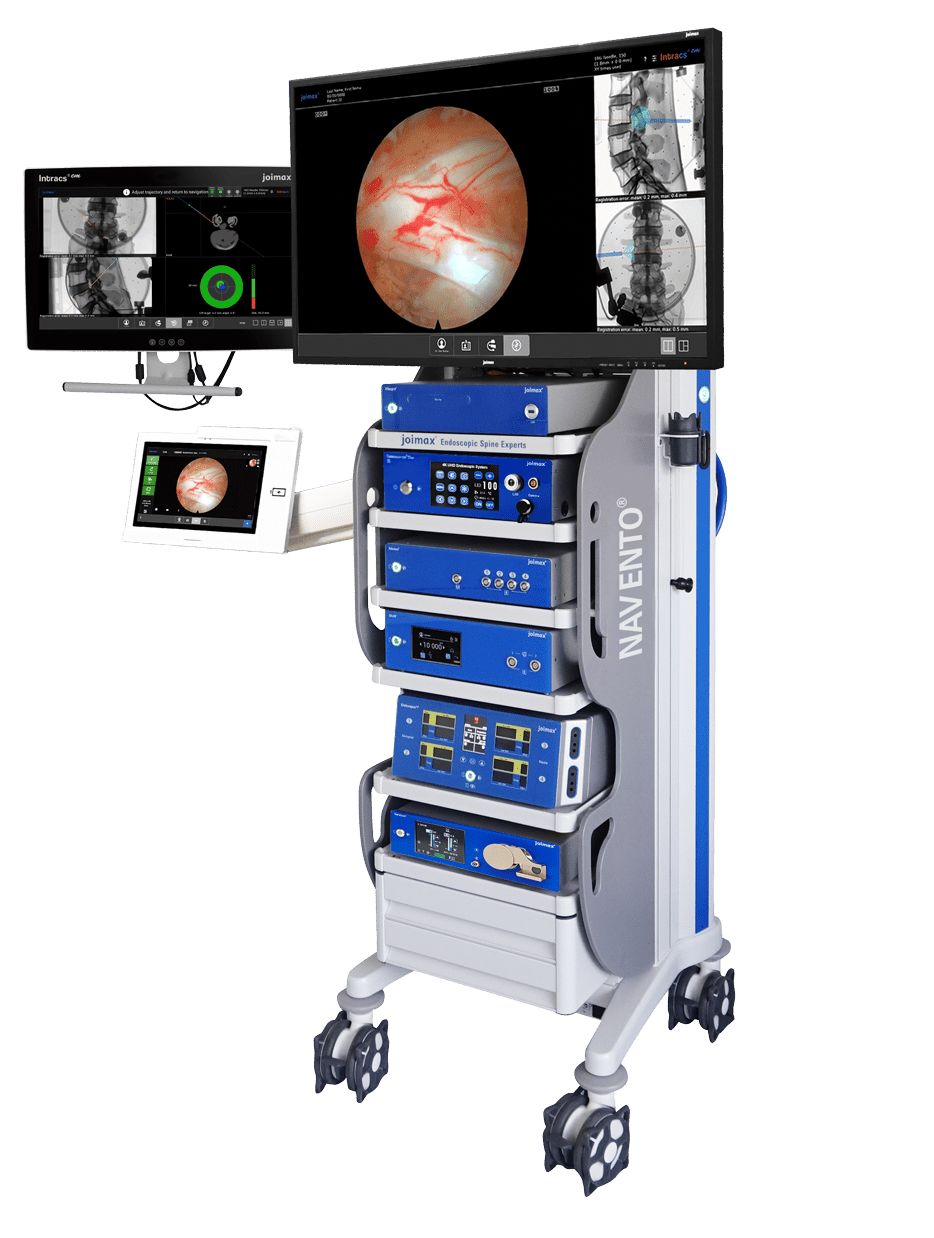

Camsource® LED and Camsource Duo® integrate best into the all-new navigation endoscopic tower: NAVENTO®.

NAVENTO® is a fully integrated and equipped endoscopic tower including all the joimax® 4th generation devices required for endoscopic access.

It offers the complete package with latest technology and coordinated functionalities of all devices.

This enables the user to master endoscopic spinal surgery in all its diversity and offers growth potential for the expansion of skills and indications.

NAVENTO® knows no boundaries!